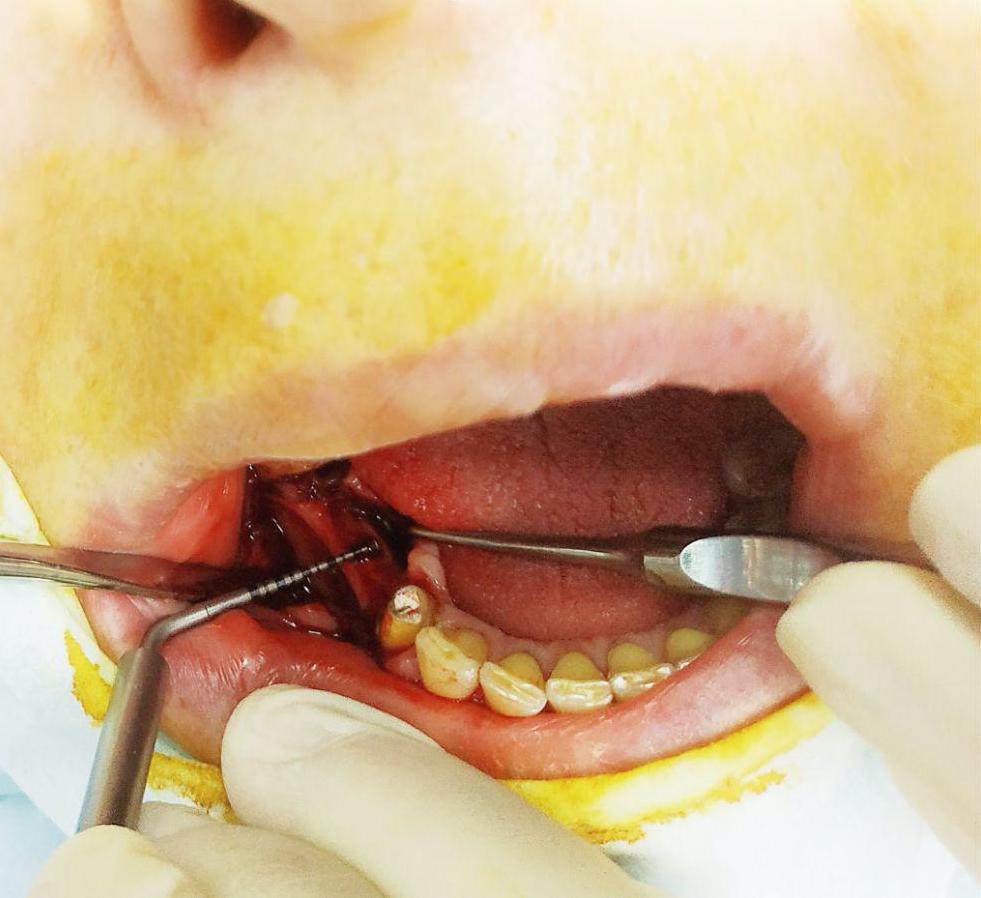

Лечение: Принято решение о пересадки ее собственной кости из угла челюсти. Отслоение слизисто-надкостничного лоскута. Забор блока кости в области угла челюсти. Остеопластика блоками + ксенографт. Установка двух имплантов. Наложение швов.